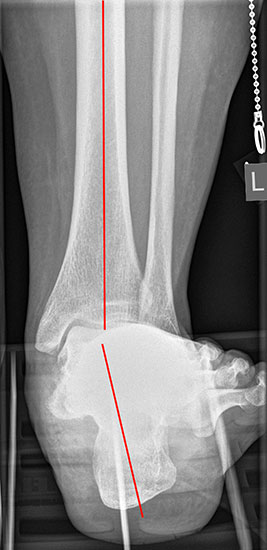

Röntgenaufnahmen des Fußes d.p., streng seitlich und schräg unter Belastung. Saltzmann Aufnahme zur Beurteilung der Rückfussachse.

Operationsplanung anhand der Röntgenaufnahmen unter Beachtung wichtiger radiologischer Landmarks wie Rückfussachse, Metatarsale I – Talushals-Achse im dp und lateralen Strahlengang (Abbildung 1 und 2).

Abbildung 2